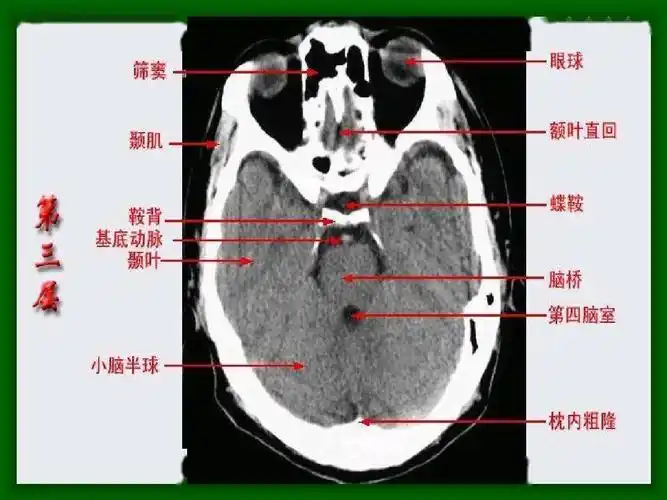

头颅ct 解剖图谱,人手一份